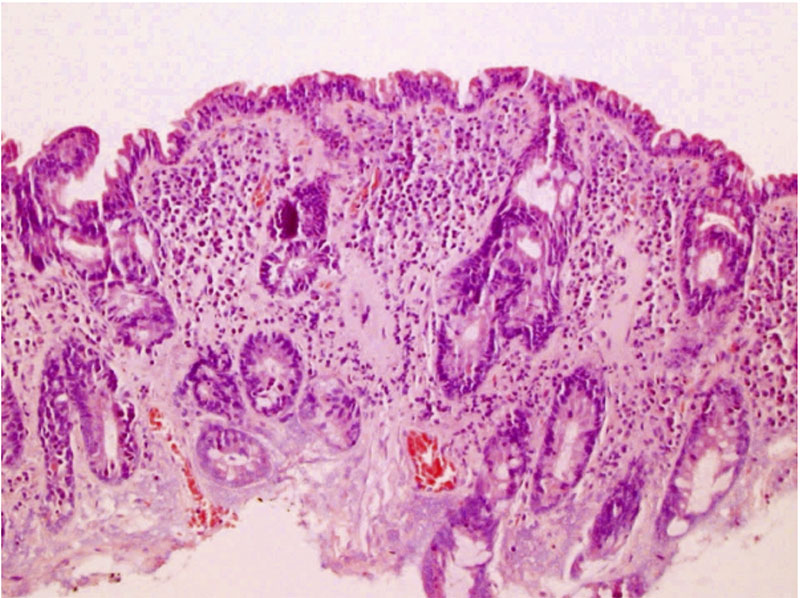

När perorala biopsikapslar för provtagning på tunntarmens slemhinna introducerades under 1960-talet blev det möjligt att påvisa de typiska ljusmikroskopiska slemhinneförändringar som finns hos patienter med celiaki (se bild ovan). Man kunde också visa att tunntarms­förändringarna läkte ut efter behandling med glutenfri kost.

Histologisk bild av duodenalslemhinna: total villusatrofi.

Histologisk bild av duodenalslemhinna: normalt utseende.